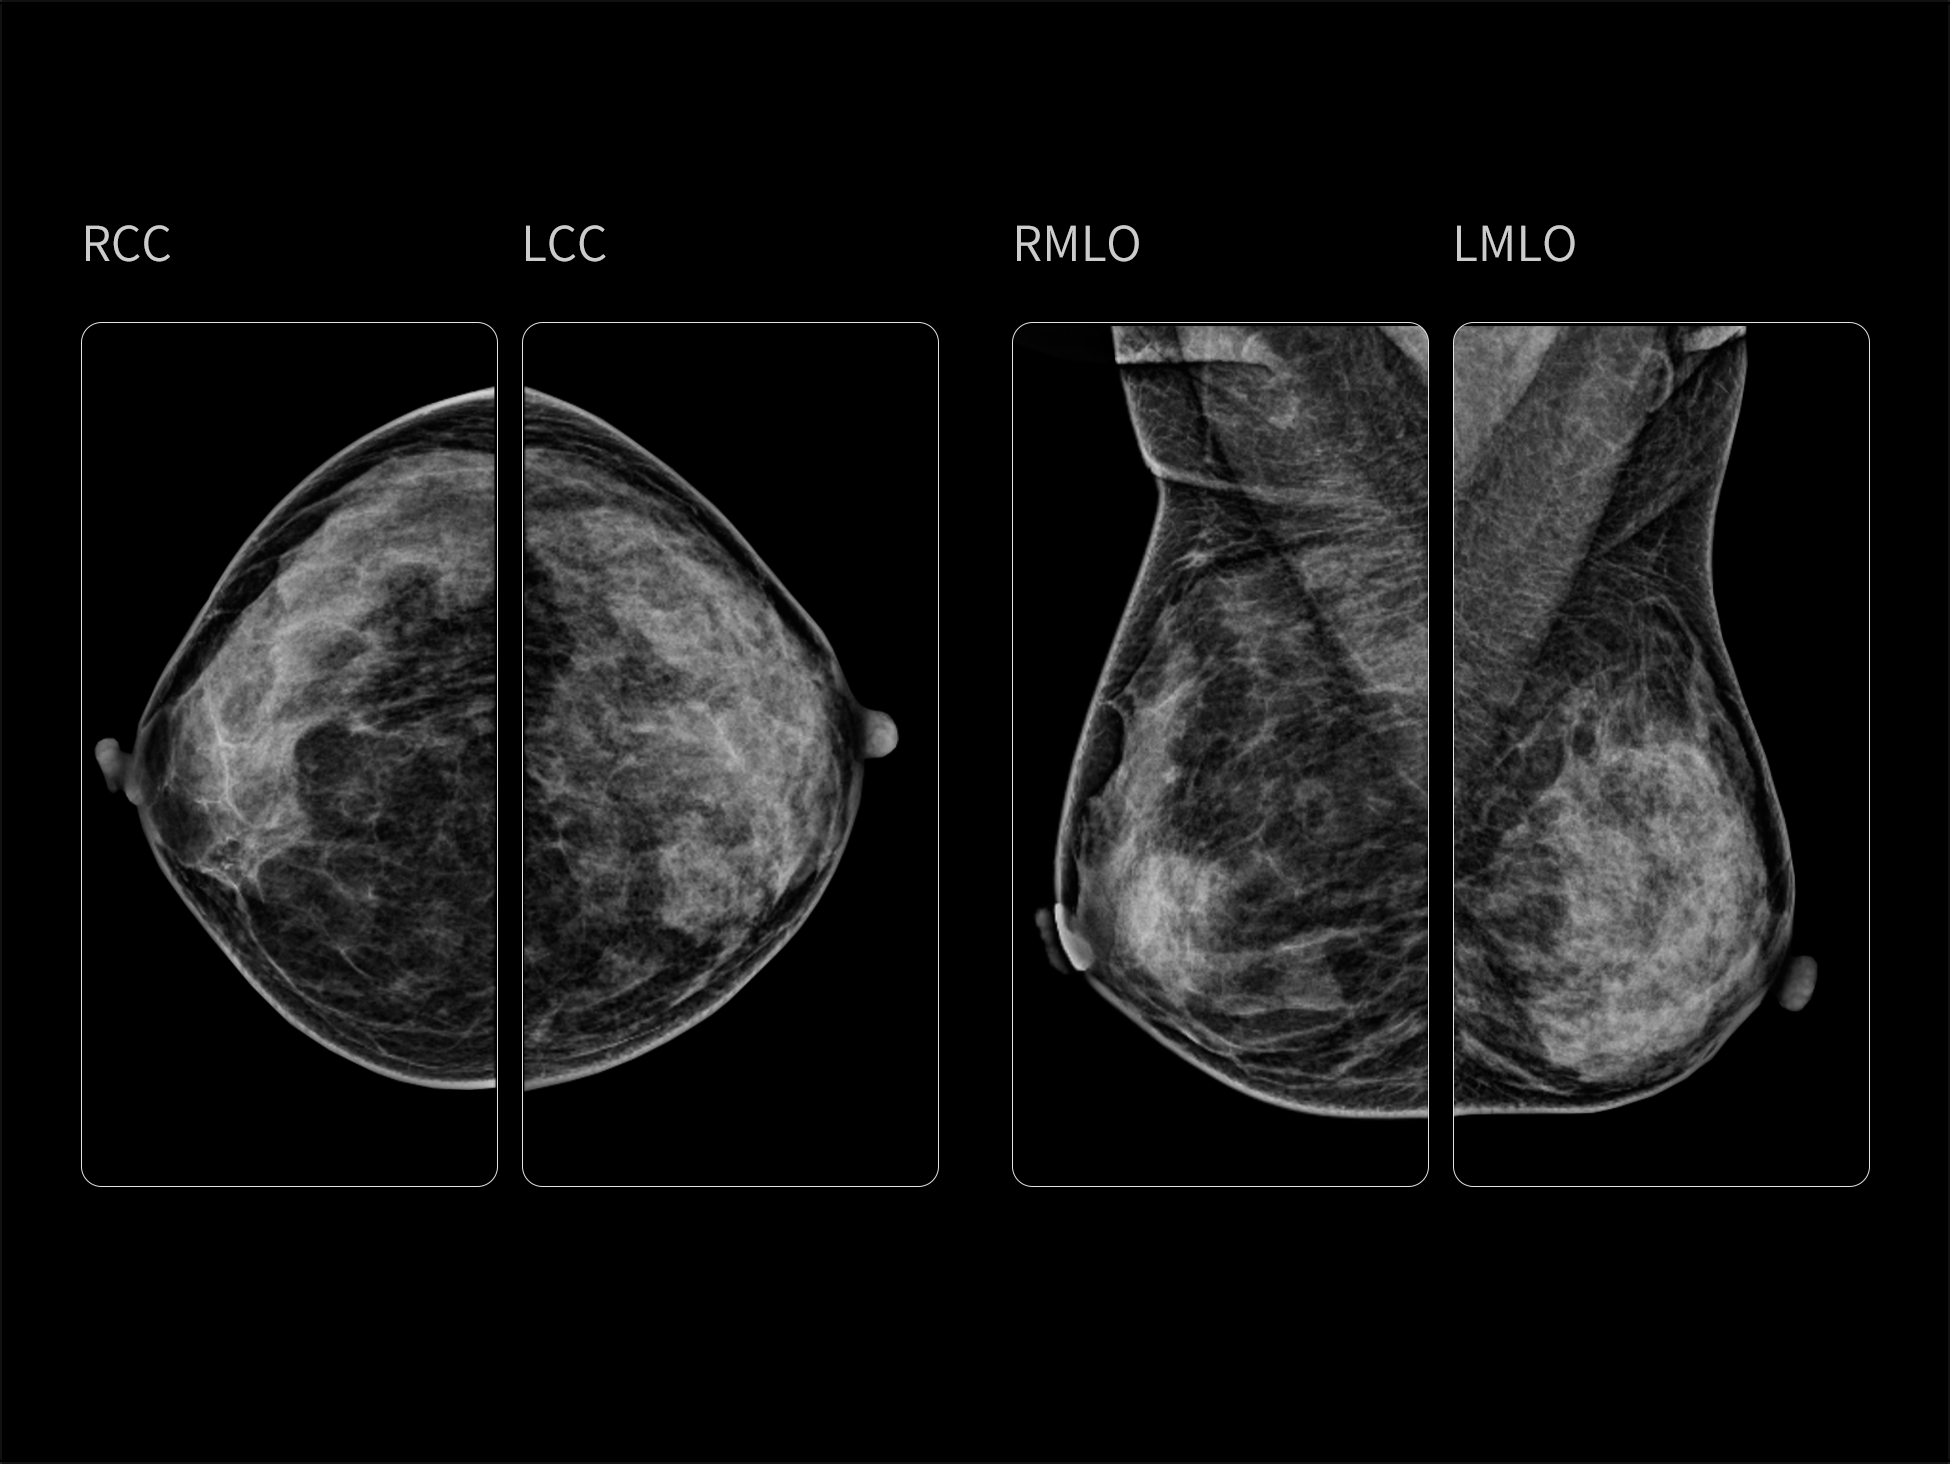

- Optimized System with An Outstanding Image Chain